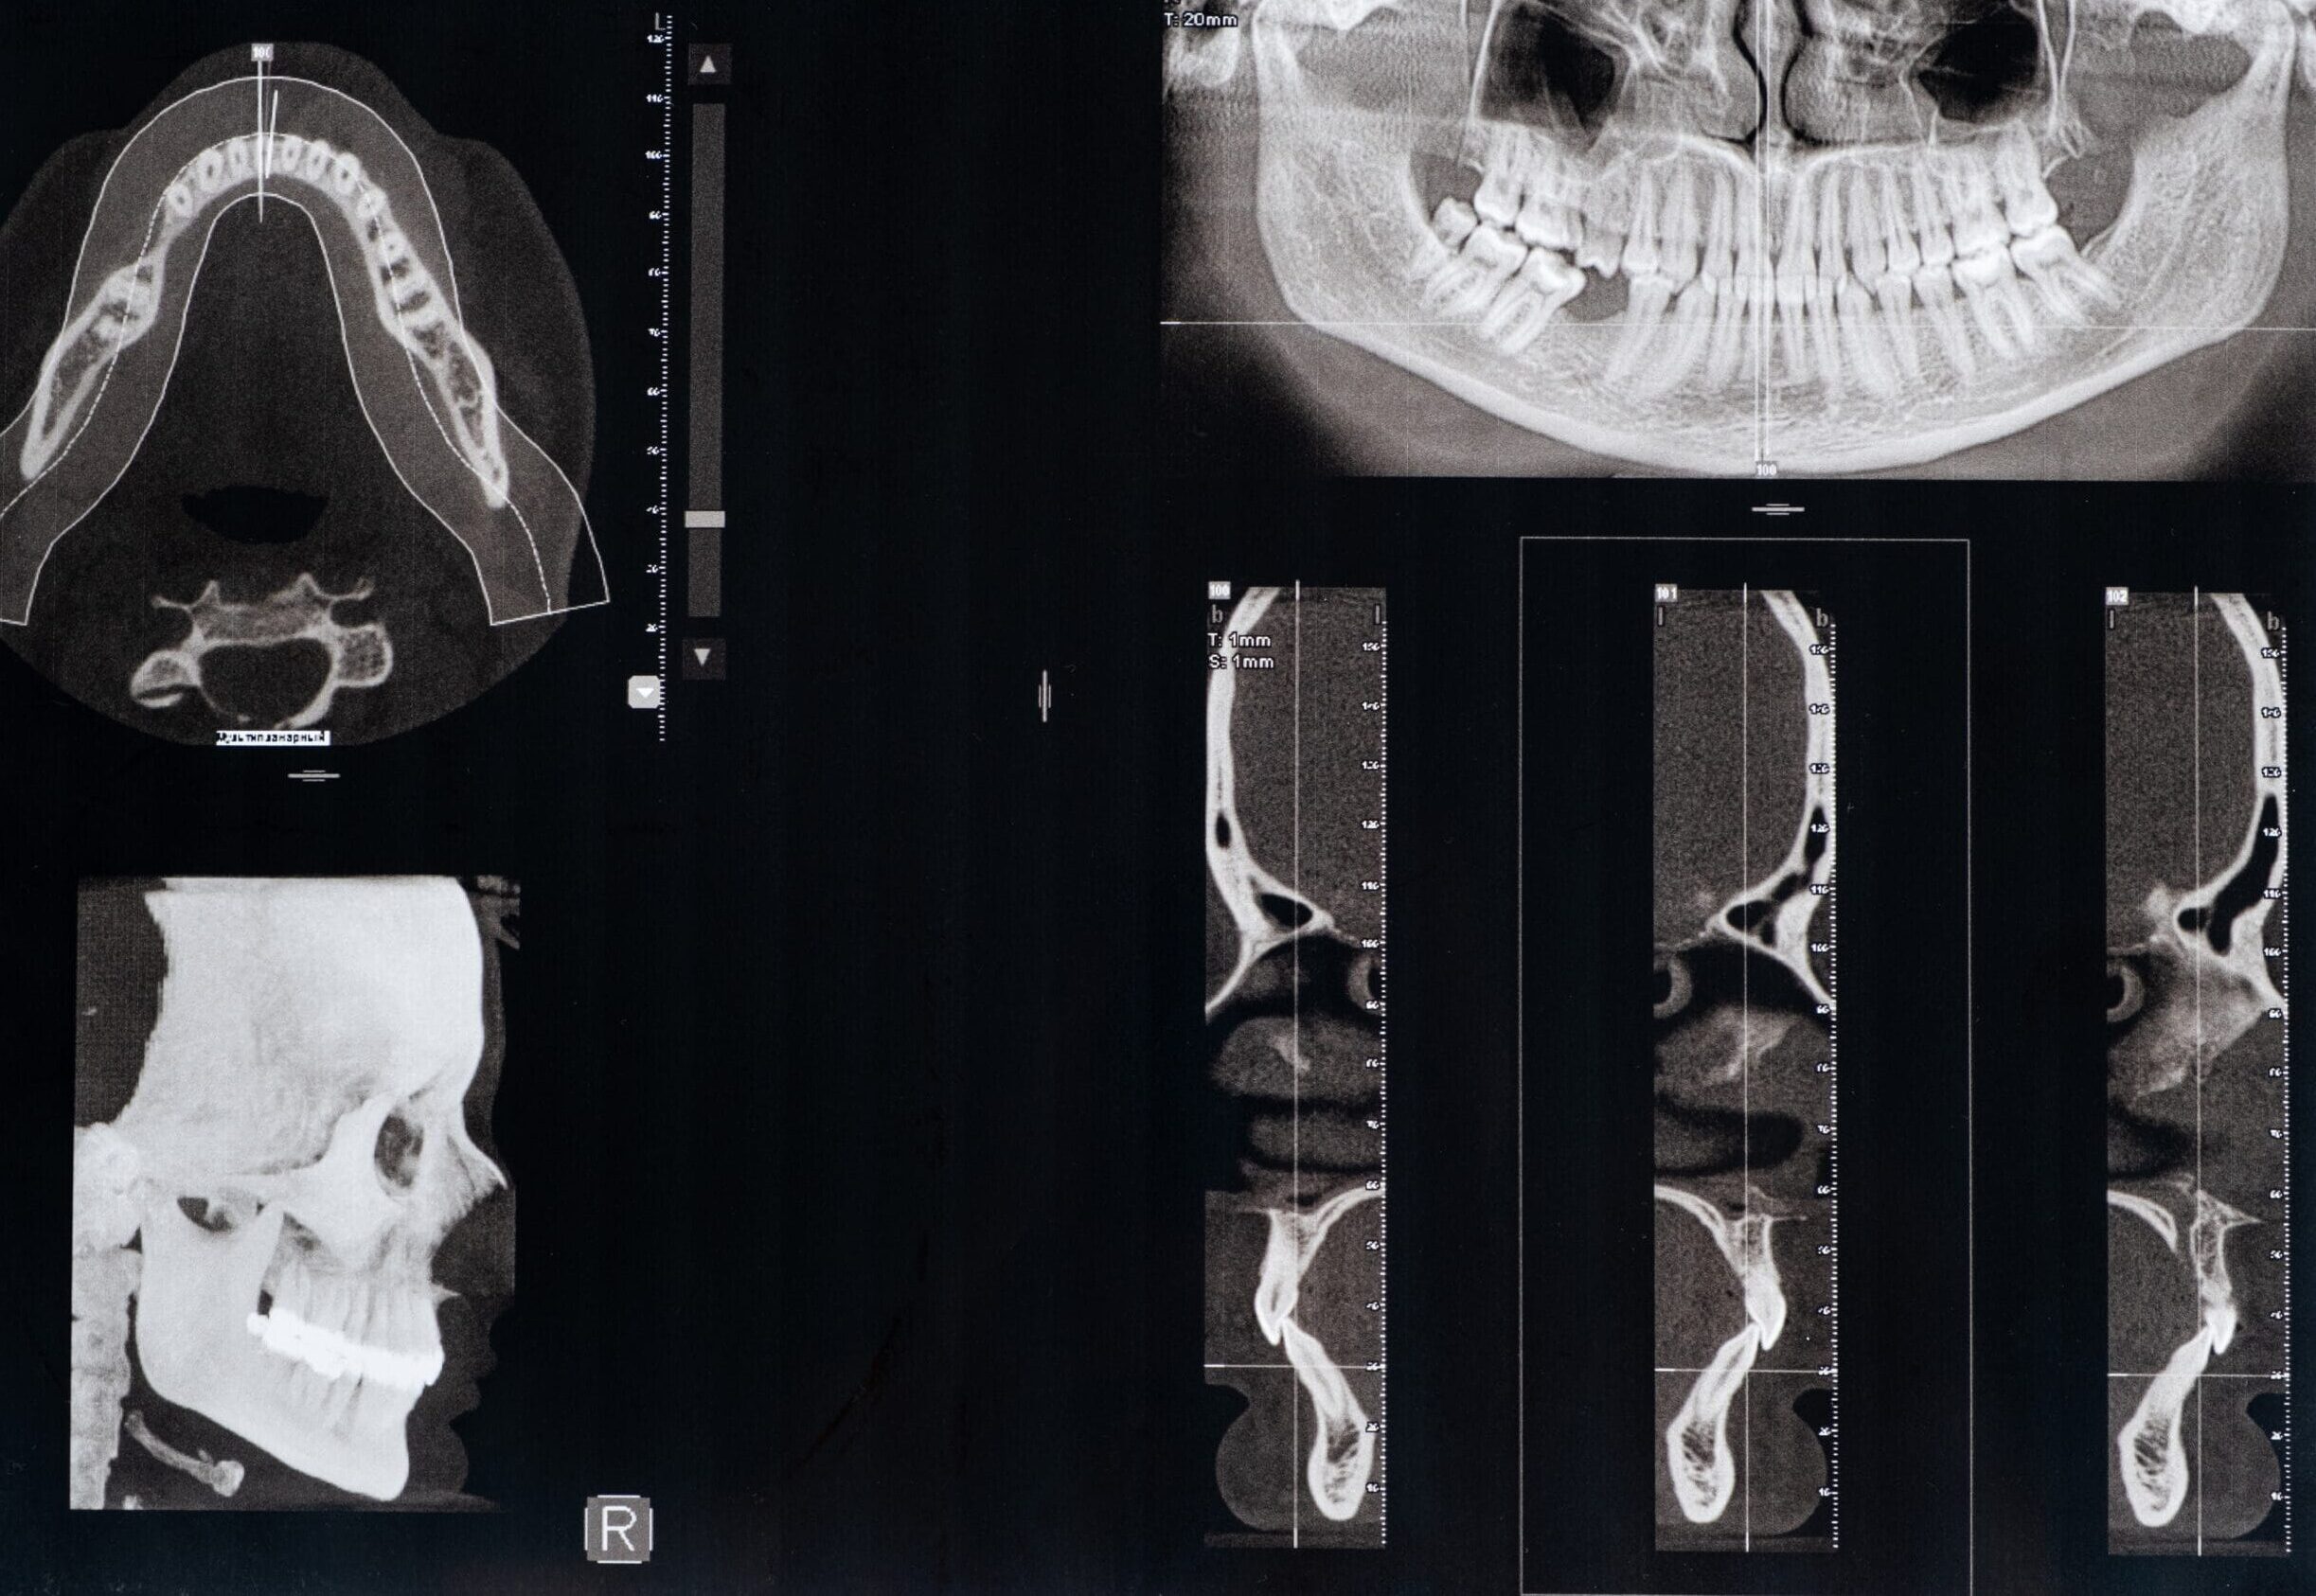

The Carestream 9300c produces clear, crisp pictures of your jaw and mouth, and it does so with greater speed than many other CT scanners. This isn’t just a technical improvement; these images are crucial for diagnoses and the creation of a treatment plan for your implants, TMJ treatment and diagnosis.

When placing dental implants, it’s vital to have a clear view of the area where the implant is to be placed. The Carestream 9300c gives Dr. MacPhail a clear view of the underlying jaw structure and the surrounding vital structures. This is especially helpful for guided tissue surgery when placing implants and identifying and correcting existing implant problems.

A CBCT scan is essentially a series of images taken in slices to accurately present a picture of the anatomy. Dr. MacPhail always makes sure to keep that amount of radiation as small as possible. With the Carestream 9300c CT scanner, Dr. MacPhail can dramatically reduce the amount of radiation her patients are exposed to when they undergo a CBCT scan.

Radiation doses are expressed using a unit of measurement known as the “millisievert,” or mSv. Most multi-detector CBCT scans require a radiation dose of between 0.8 and 2.0 MSV to produce a clear image. With the Carestream 9300c, however, Dr. MacPhail can image with a dose that ranges from .04 to .19 MSV, depending on what is being scanned. This lower dosage means less exposure!